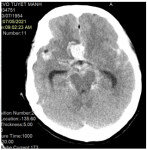

- The head CT show a diffuse subarachnoid hemorrhage was found in the sylvian fissure, basal cistern, concentration on interhemispheric frontal lobe.

- The head CT after 18h of intervention show no futher bleeding